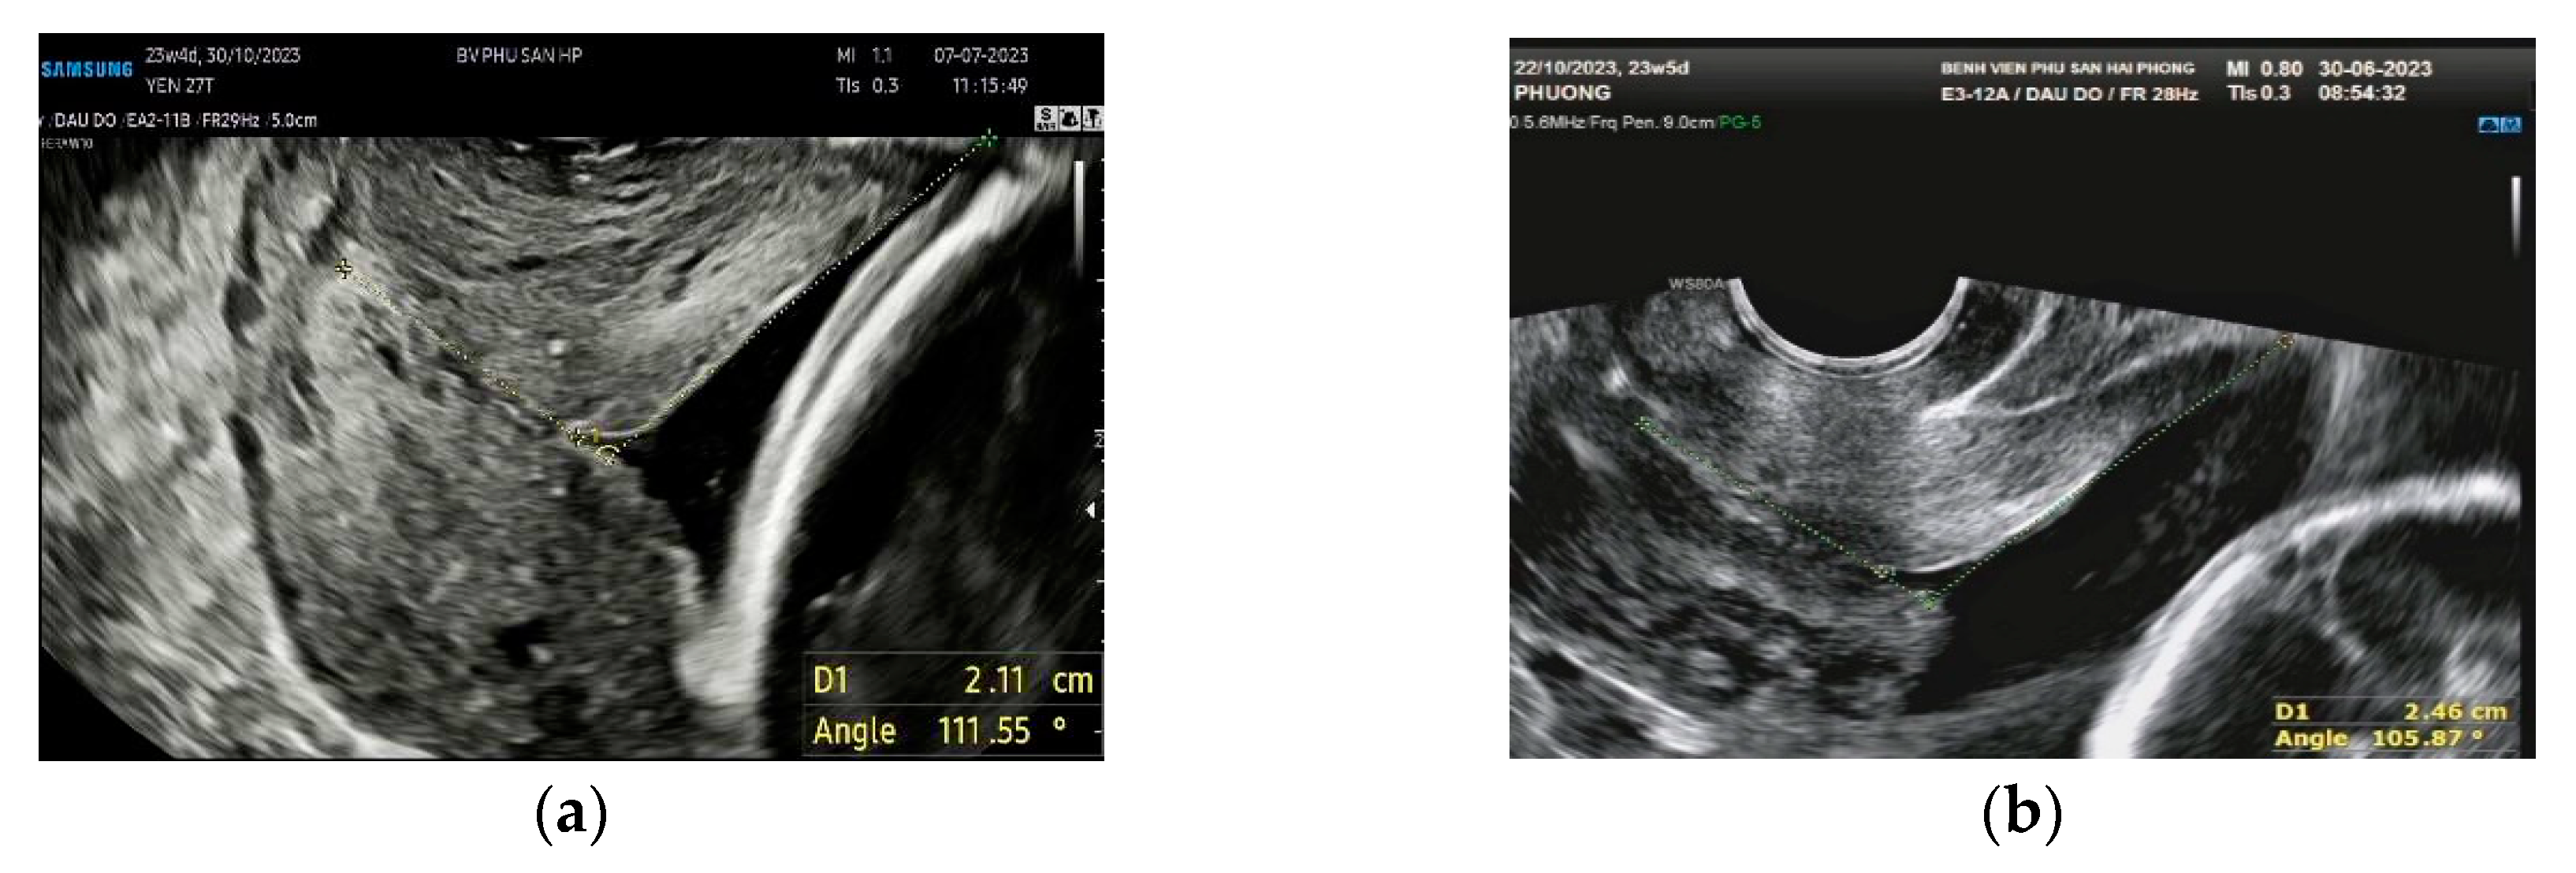

In the case of a funnel-shaped internal os, the first line of the UCA was placed to measure CL, and the second line was drawn from the innermost part of the cervix that can be measured and extended tangentially to the lower anterior inner uterine (Figure 3).

Figure 3. (a) 23+4 weeks pregnant with V-shaped internal os, CL of 21.1 mm, and UCA of 111.5o; (b) 23+5 weeks pregnant with Y-shaped internal os, CL of 24.6 mm, and UCA of 105.87o.